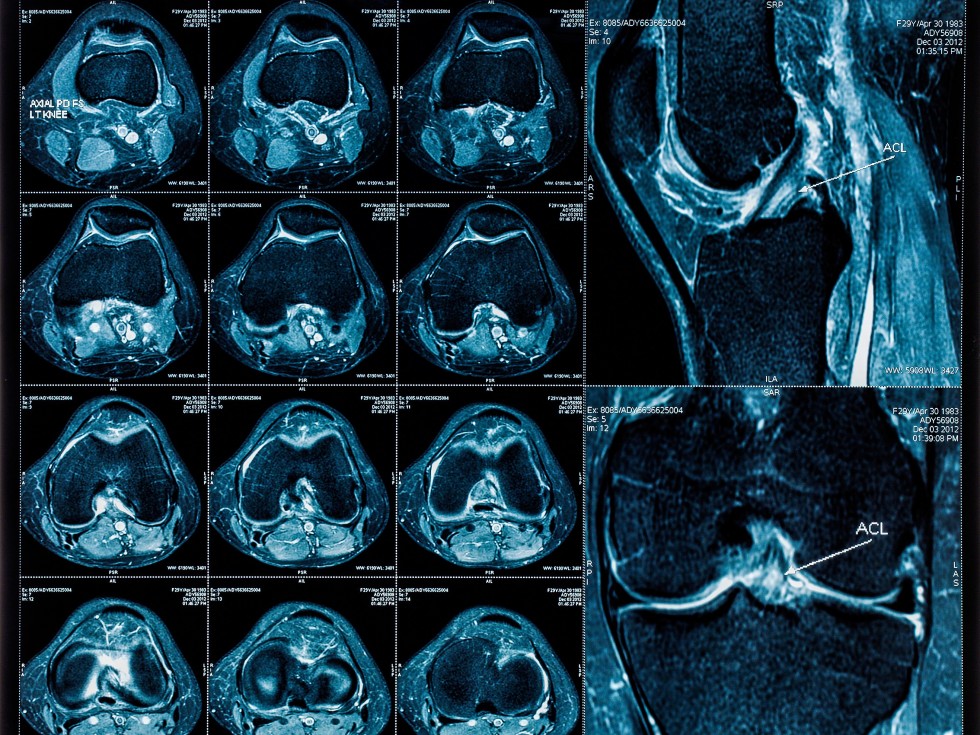

MRI Knee

Magnetic resonance imaging, or MRI, is a method of producing detailed pictures of organs and body tissues by exposing a patient to radio waves in a strong magnetic field. The field is measured and analyzed by a computer, which forms two- or three-dimensional images that may be viewed on a monitor. Because it uses radio waves and a magnetic field rather than x-rays, there is no exposure to radiation. An MRI can be used to examine every joint in the body. Most commonly the spine, knee and shoulder are viewed, but the procedure also can be performed on the hips, wrists, and hands. An MRI is often the best choice when examining joints because it provides very clear pictures of the soft tissue near and around the bones. The procedure often is used to diagnose sports-related injuries and work-related injuries.